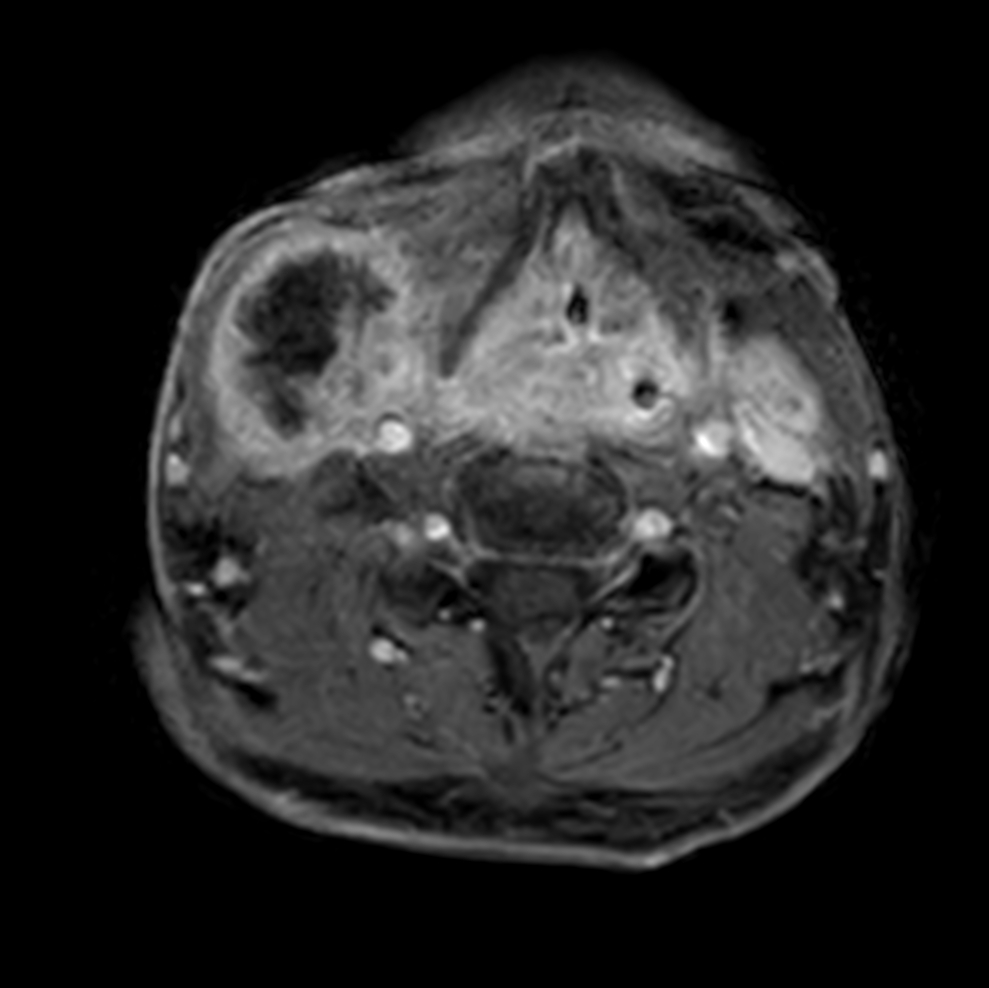

Axial T1w mDIXON XD - pre-gado